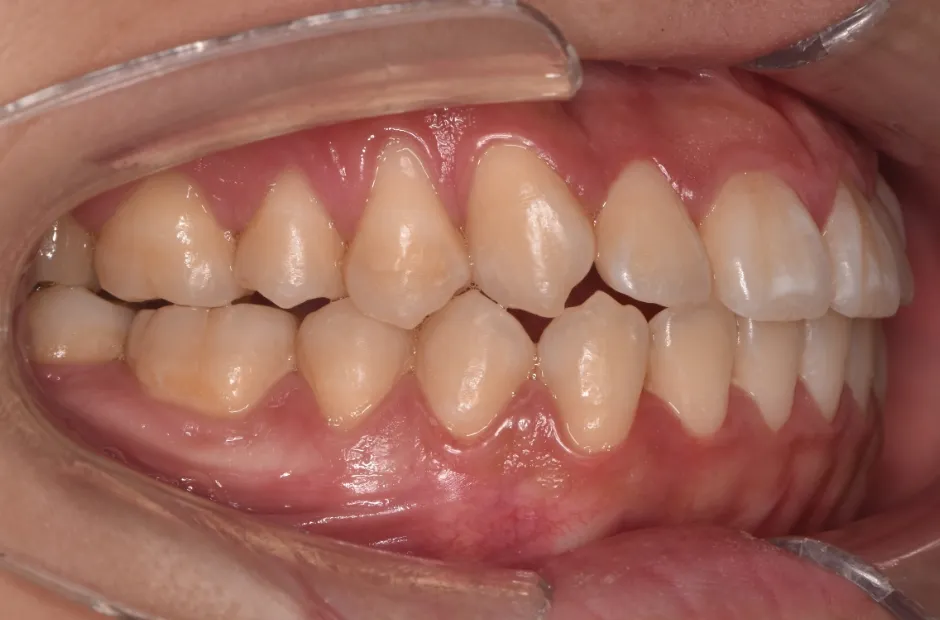

叢生

| 診断名・主訴 | 叢生 |

|---|---|

| 年齢・性別 | 43歳・女性 |

| 治療期間・回数 | 2年7か月 27回 |

| 治療に用いた主な装置 | 舌側矯正 |

| 抜歯部位 | 両顎4,4 |

| 治療費 | 100万円(税抜) |

| リスク・副作用 | 装置による違和感・疼痛・歯肉退縮・歯根吸収・虫歯のリスクなど |

治療前